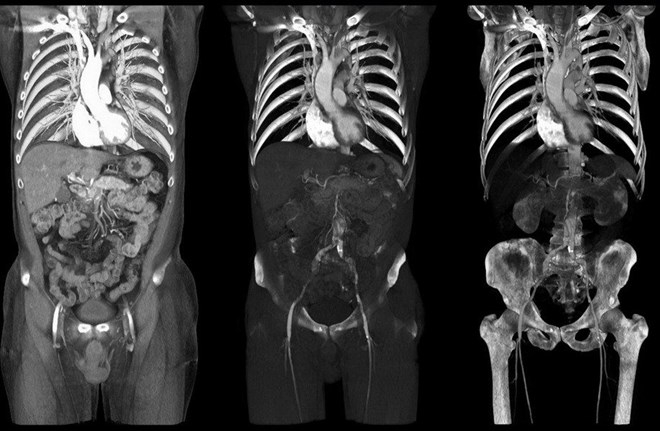

Tờ Boston Globe cho biết bác sỹ này đã tiến hành chụp CT trước khi phẫu thuật, kết quả cho thấy có khối u trên thận. Tuy nhiên, kết quả chụp này là của một bệnh nhân khác.